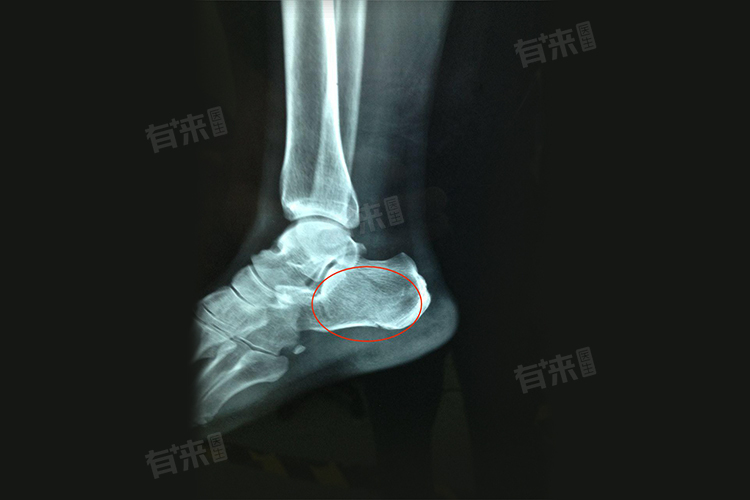

没有脚后跟骨裂怎么治疗最好的说法,脚后跟骨裂是一种常见的足部损伤,治疗方案需根据骨裂的严重程度、患者的具体状况以及医生的建议来综合制定,处理措施主要包括固定包扎等。